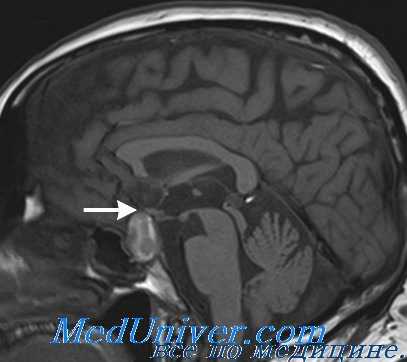

- Методы медицинской визуализации. Прицельный рентгенологический снимок турецкого седла позволяет выявить уменьшение размеров железы. Более подробную информацию о структуре и изменениях органа предоставляют томографические методики (МРТ, компьютерная томография).

- Нейровизуализация. Чтобы обнаружить органические поражения гипоталамо-гипофизарной зоны, проводится рентгенография турецкого седла, МРТ или КТ головного мозга. При необходимости обследование дополняется церебральной ангиографией, электроэнцефалографией.